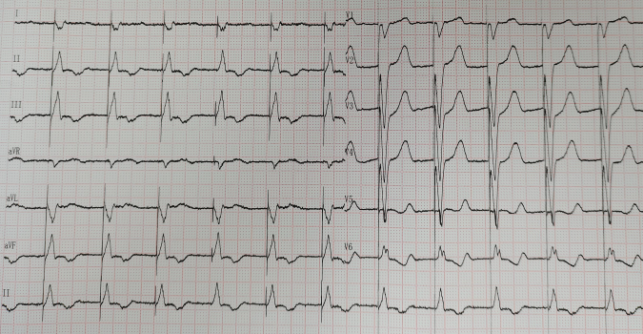

病例1

患者,58岁,女性,因“活动后气促伴心跳加速3月入院”,诊断为“风湿性二尖瓣狭窄瓣关闭不全(重度)、三尖瓣关闭不全(中度)、持续性心房颤动、心功能III级”,遂行二尖瓣机械瓣瓣膜置换术+三尖瓣成形术+心脏射频消融术+左心耳切除术,术后即刻房颤消失,恢复良好。

术后即刻心电图